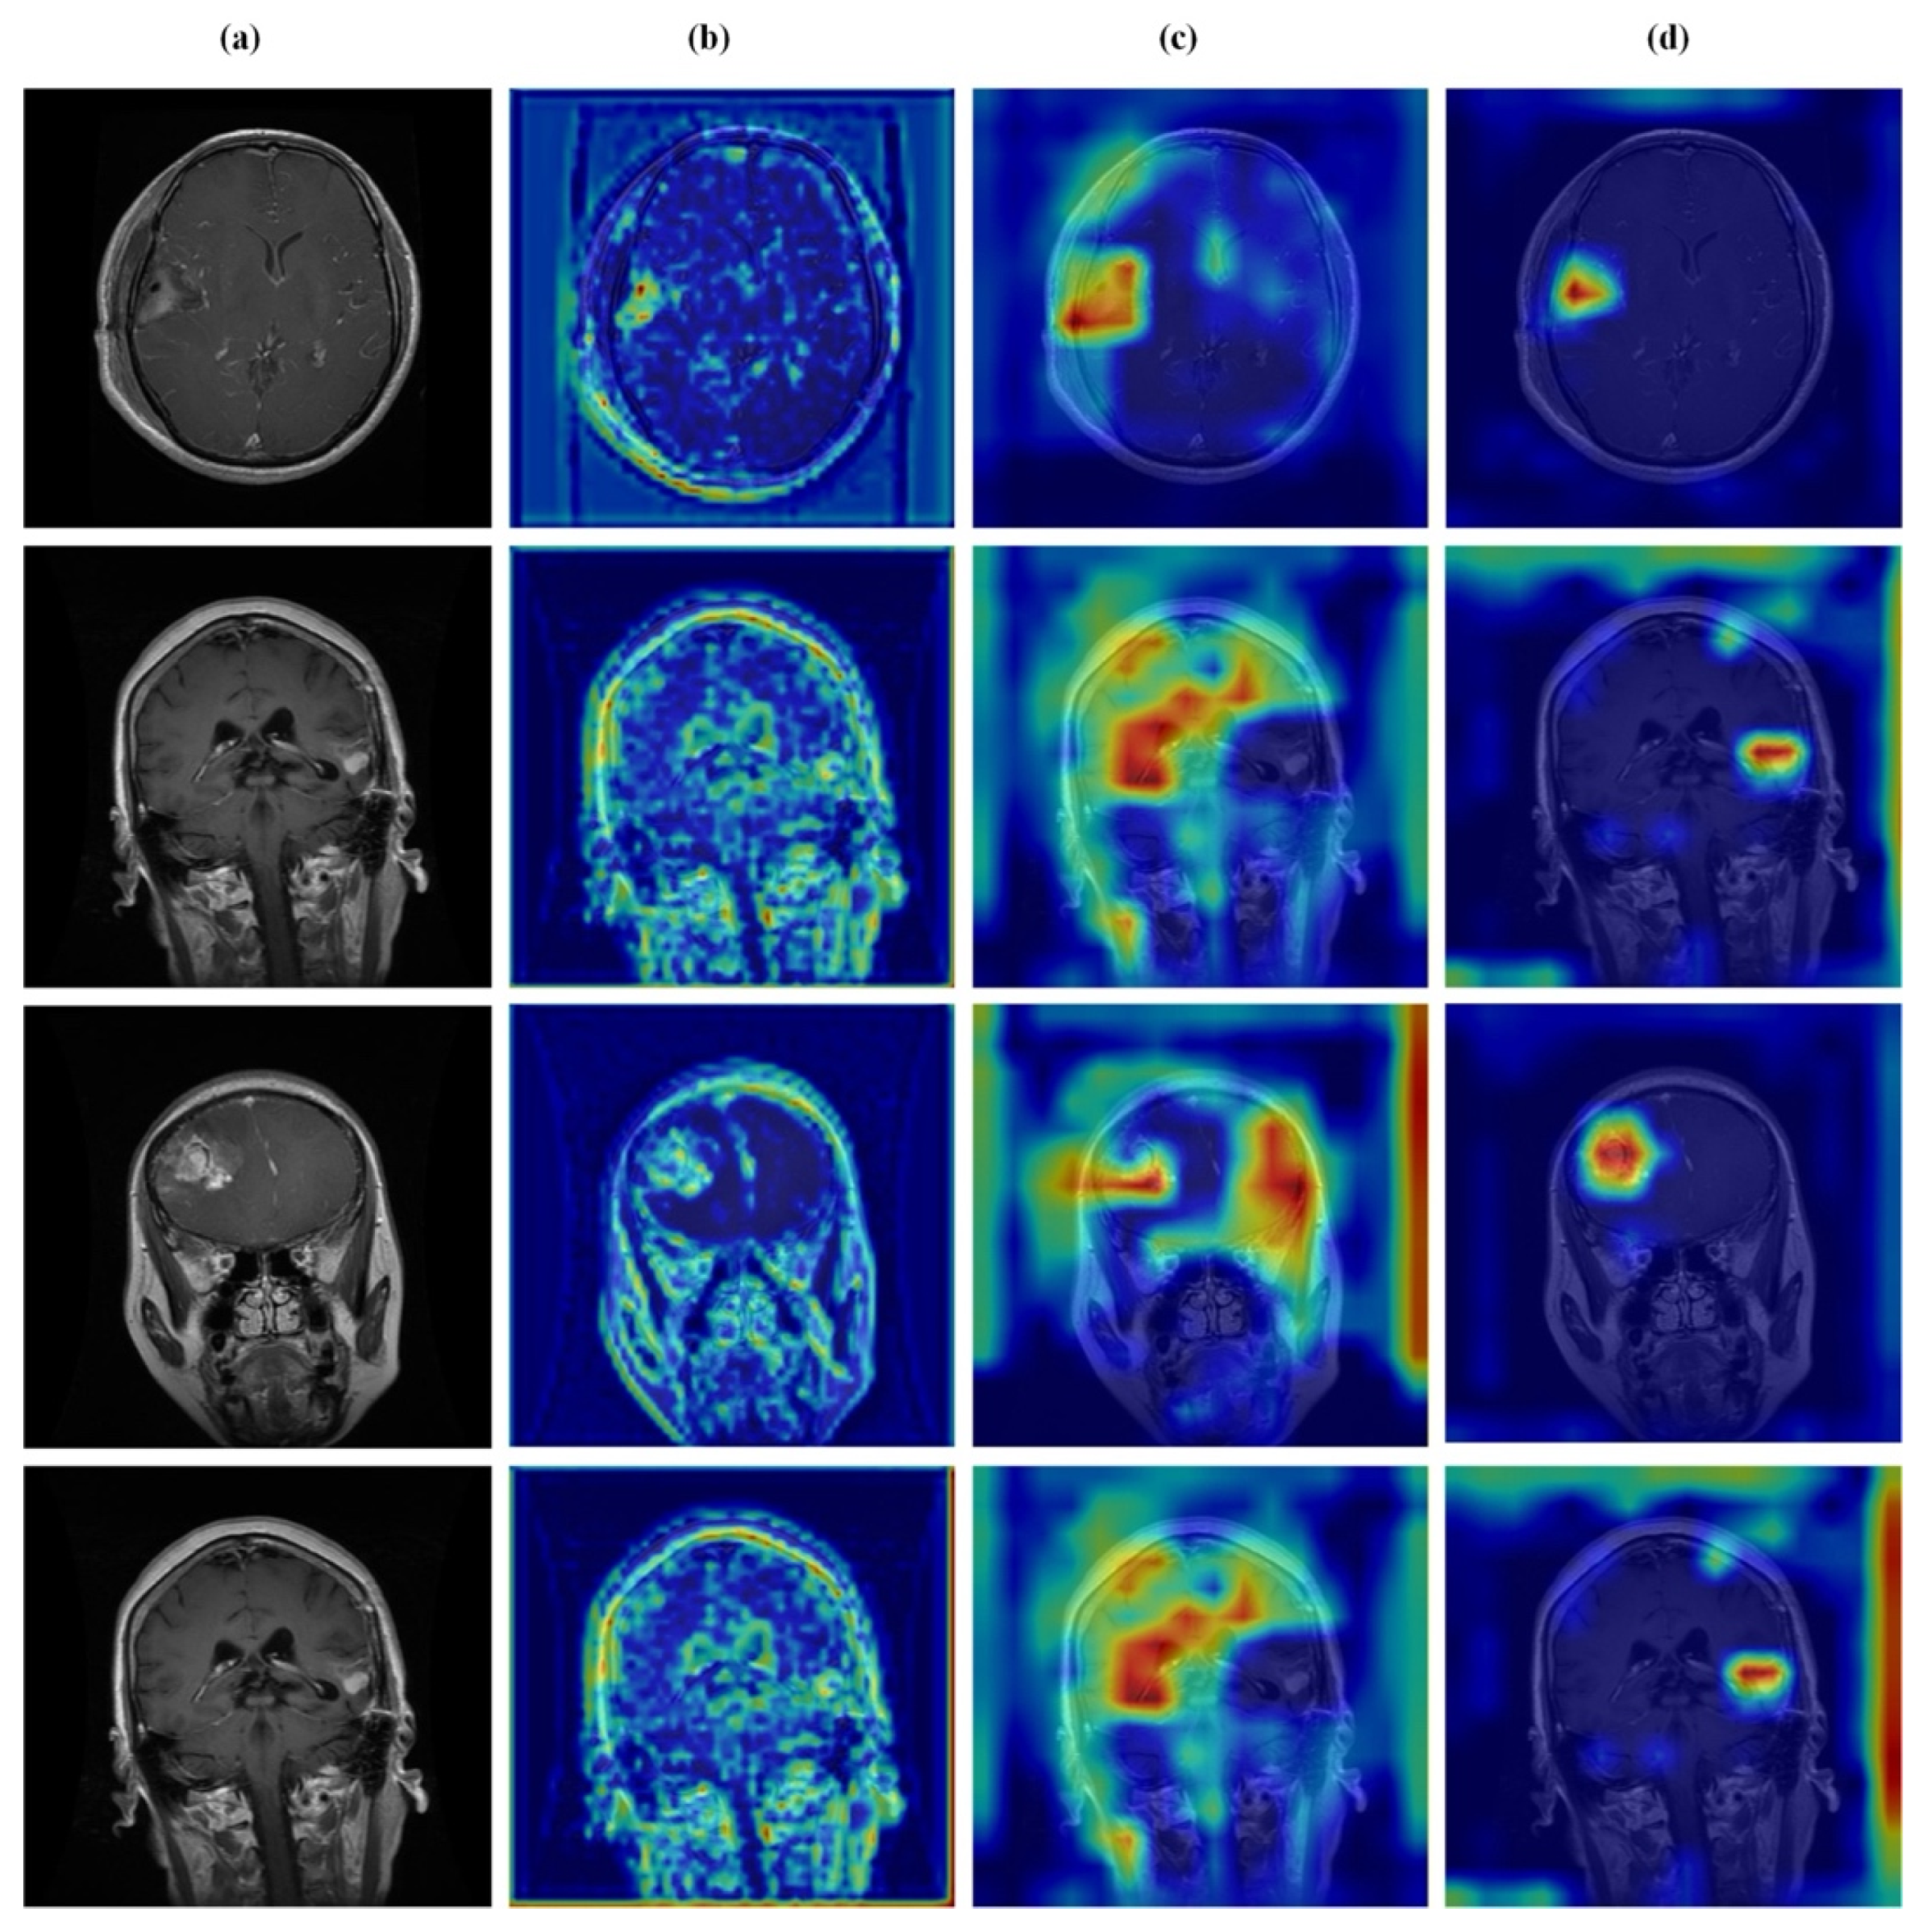

Figure 12, Figure 13, Figure 14 and Figure 15 present Grad-CAM visualizations that trace the hierarchical feature learning of the proposed model across the four classes. Columns are organized as (a) input, (b) high-level features, (c) mid-level features, and (d) low-level features. In (d), the network emphasizes primitive cue edges, intensity transitions, and fine textures capturing sulcal boundaries, skull edges, and generic tissue patterns. Progressing to (c), activations become more structured and context-aware, highlighting coherent anatomical regions and diffuse hyperintense areas that provide spatial context for lesion localization. At (b), class-discriminative focus emerges with responses that contract tumor-centric hotspots for glioma and meningioma and to the sellar region for pituitary cases, while no_tumor images exhibit suppressed high-level responses, reflecting the model’s rejection of false lesion cues. This bottom-to-top progression from generic edges to task-specific evidence explains the model’s improved decision reliability and aligns with the multi-task design that encourages precise, clinically meaningful attention.

Figure 12.

Visual representation of feature activations in no tumor cases. (a) input, (b) low-level features, (c) mid-level features, and (d) high-level features.

Figure 13.

Visual representation of feature activations in glioma tumor cases. (a) input, (b) low-level features, (c) mid-level features, and (d) high-level features.

Figure 14.

Visual representation of feature activations in meningioma tumor cases. (a) input, (b) low-level features, (c) mid-level features, and (d) high-level features.

Figure 15.

Visual representation of feature activations in pituitary tumor cases. (a) input, (b) low-level features, (c) mid-level features, and (d) high-level features.